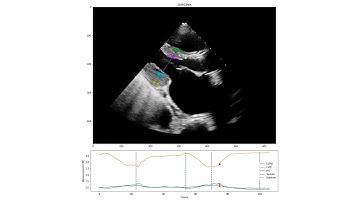

Python Machine Learning Projects - Predict Left Ventricular Diastolic Dysfunction - ClickMyProject